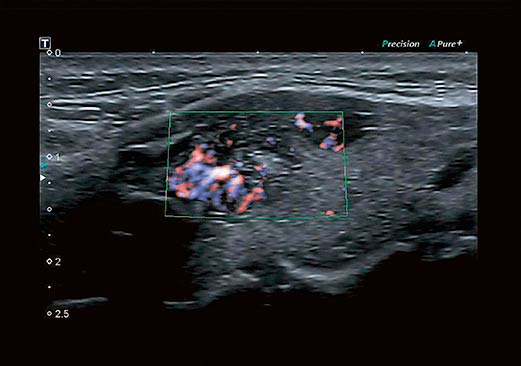

Технология визуализации микроциркуляторного русла (SMI), разработанная корпорацией Canon Medical Systems, расширяет диагностические возможности ультразвуковых систем Aplio. Позволяет визуализировать низкоскоростной кровоток в микрососудах.

Технология Advanced Dynamic FlowTM (ADF) обеспечивает высочайшее пространственное разрешение в режиме цветового допплеровского картирования, позволяя с высокой точностью и детализацией выявлять мелкие сосуды и зоны со сложным характером кровотока, в полной мере сохраняя качество изображений, присущее B-режиму.

Цветовая энергетическая ангиография сочетает чувствительность и глубину проникновения энергетического допплера с информацией о направлении кровотока, полученной при цветовом допплеровском картировании, позволяя более точно определять сосудистый рисунок ткани.

Технология визуализации микроциркуляторного русла (SMI), разработанная корпорацией Canon Medical Systems, расширяет диагностические возможности ультразвуковых систем Aplio. Позволяет визуализировать низкоскоростной кровоток в микрососудах.